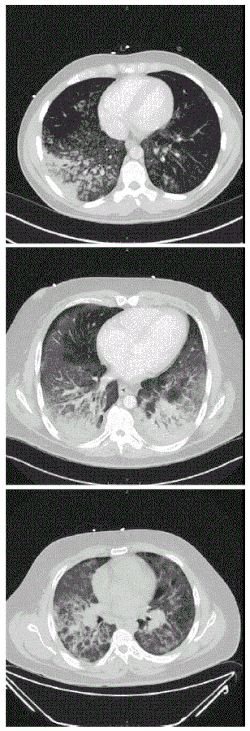

![]() Изображения компьютерной томографии, показывающие диффузные инфильтраты в лёгких у трёх пациентов, 2019 год | |

Компьютерная томография больных зафиксировала лёгочный инфильтрат: диффузные или располагающиеся в нижних отделах уплотнения по типу «матового стекла» с сохранением структуры в субплевральных (78,1 %), лобулярных (59,4 %) или перибронховаскулярных (40 %) областях. Последнее встречалось у более молодых пациентов и не являлось характерным при остром повреждении лёгких[11][12]. При поступлении в больницу у всех пострадавших наблюдалось повышенное количество лейкоцитов с преобладанием нейтрофилов и отсутствием эозинофилии[4][10][13]. Плазма потребителей электронных сигарет также показывала повышенный уровень гидроксиэйкозатетраеновой кислоты и различных эйкозаноидов[6].